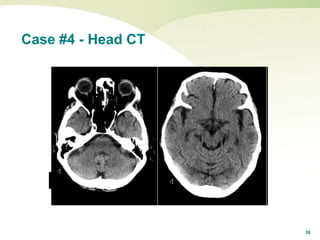

Case #4 - Head CT

39

Cerebral Venous Vein Thrombosis

 Points to consider in this high-risk case:

 26 y/o female with no history of migraine

and 2 visits to ED for headache.

 Heavy exercise predisposes to dehydration.

 NuvaRing / IUD not often reported as a medication.

 CVST is notoriously challenging to diagnosis.

 Supine positioning that worsens headache is

worrisome for increased intracranial pressure.

 Initial non-con head CT on second visit was NOT

normal.

 High index of suspicion is necessary.